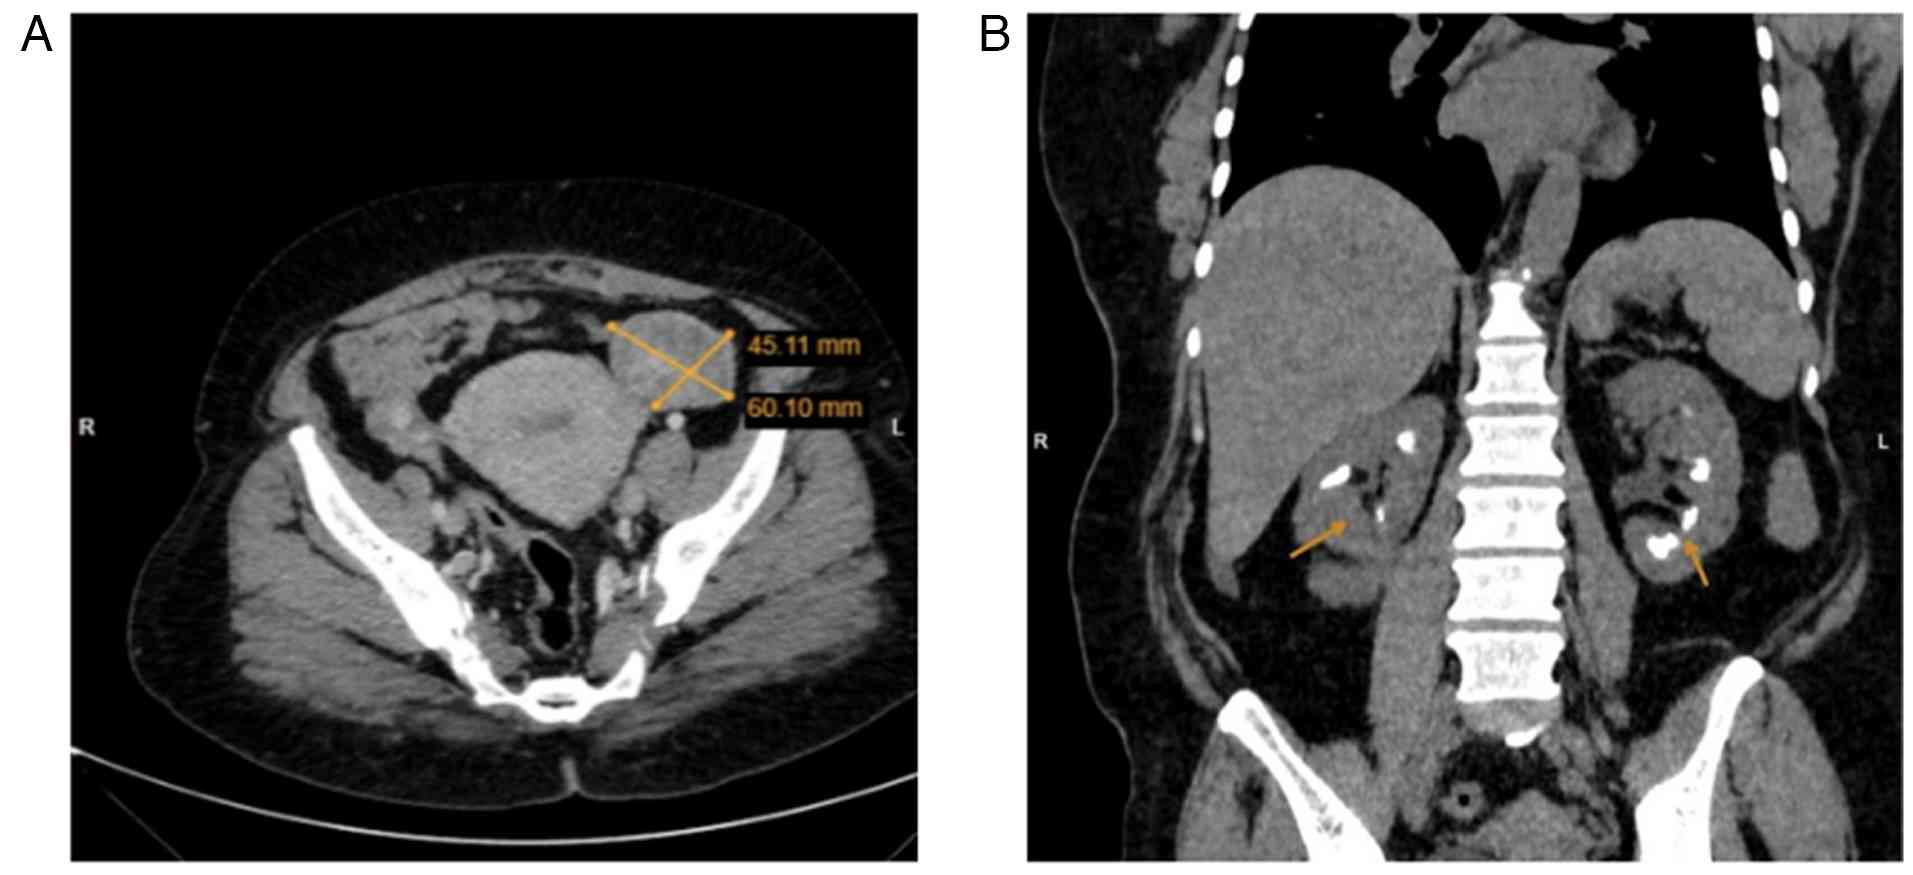

A contrast-enhanced computed tomography (CT) scan of the chest, abdomen, and pelvis revealed two right breast masses, the largest measuring 4 cm, with no evidence of chest wall invasion. Pathological right axillary lymph nodes were present across all levels, with the largest measuring 1.6 cm, while no enlarged internal mammary lymph nodes were detected. Additionally, bilateral adnexal masses were identified, raising the suspicion of primary ovarian cancer or metastatic disease with associated peritoneal deposits. Multiple bilateral renal calcifications were noted in the medullary region, suggesting medullary nephrocalcinosis (Fig. 3). To further evaluate the ovarian and peritoneal lesions, a diagnostic laparoscopy was performed, and biopsies were taken. A histopathological analysis was then performed. Sections (5-µm-thick tissue sections were fixed in 10% neutral-buffered formalin at room temperature for 24 h and subsequently embedded in paraffin. The sections were then stained with hematoxylin and eosin (Bio Optica Co.) for 1-2 min at room temperature and examined under a light microscope (Leica Microsystems GmbH). The histopathological examination revealed extensive infiltration by dyscohesive sheets and cords of malignant epithelial cells embedded within a desmoplastic stroma. The tumor cells exhibited marked nuclear pleomorphism, hyperchromatic nuclei, prominent nucleoli, and frequent mitotic figures. Occasional intracytoplasmic vacuoles imparted a signet-ring-like appearance. The peritoneal deposits exhibited infiltrative epithelial cells associated with stromal desmoplasia and focal crush artifact, supporting metastatic involvement (Fig. 4). The findings of IHC were consistent with metastatic PLC of the breast. The cytological analysis of the peritoneal fluid was positive for malignancy, confirming metastatic disease. IHC staining of the ovarian and peritoneal tumor cells revealed positivity for cytokeratin 7 (CK7), GATA-binding protein 3 (GATA3) and trichorhinophalangeal syndrome type 1 (TRPS1), further supporting a breast origin for the malignancy (Figs. 5 and 6). IHC was performed on formalin-fixed, paraffin-embedded tissue sections (4 µm thickness). The sections were deparaffinized in xylene and rehydrated through graded ethanol to distilled water. Heat-induced epitope retrieval was carried out using EnVision™ FLEX Target Retrieval Solution, High pH (cat. no. K8004, Agilent Technologies, Inc.) in a pressure-based retrieval system according to the manufacturer's instructions. Endogenous peroxidase activity was blocked using EnVision™ FLEX Peroxidase-Blocking Reagent (cat. no. SM801, Agilent Technologies, Inc.). The primary antibodies were applied at the following working dilutions: CK7 (mouse monoclonal, clone OV-TL 12/30; cat. no. M7018, Agilent Technologies, Inc.) at 1:200, GATA3 (mouse monoclonal, clone L50-823; cat. no. 386M-16, Cell Marque™ Tissue Diagnostics) at 1:100, and TRPS1 (rabbit monoclonal, clone EPR16171; cat. no. ab209664, Abcam) at 1:250. All primary antibodies were diluted in antibody diluent supplied by the manufacturer and incubated according to standard laboratory protocols. Antibodies were incubated at room temperature for 30-60 min according to the manufacturer's recommendations. Immunodetection was performed using the EnVision™ FLEX detection system (cat. no. SM802, Agilent Technologies, Inc.), which employs a dextran-based polymer secondary antibody conjugated to horseradish peroxidase (HRP). This system provides species-specific secondary antibodies against mouse and rabbit immunoglobulins and was used ready-to-use (no dilution required), in accordance with the manufacturer's instructions. All immunohistochemical staining procedures, including primary antibody incubation and polymer-based secondary antibody incubation, were carried out at room temperature (20-25˚C). Primary antibodies were incubated for 30-60 min at room temperature (20-25˚C), as recommended by the respective manufacturers. The EnVision™ FLEX HRP-labeled polymer secondary antibody was applied for 20 min at room temperature. Visualization with 3,3'-diaminobenzidine (DAB) chromogen (cat. no. DM827, Agilent Technologies, Inc.) was performed for 5-10 min, with microscopic monitoring to ensure optimal signal development. Nuclear counterstaining was performed using hematoxylin solution (cat. no. 05-M06002, Bio Optica S.p.A.) for ~1-2 min at room temperature, followed by rinsing in running tap water, dehydration through graded alcohols, clearing in xylene and mounting. The patient was diagnosed with primary invasive PLC of the right breast, with metastatic involvement of the right axillary lymph nodes, bilateral ovaries and peritoneum. Based on clinical, radiological and histopathological findings, the disease was staged as cT2N3M1 according to the TNM classification system.

Contrast-enhanced CT images. (A) Axial

post-contrast CT scan demonstrating a heterogeneously enhancing

complex cystic lesion in the left adnexa, measuring 60x45 mm,

consistent with metastatic involvement from primary invasive

lobular carcinoma of the breast. (B) Coronal non-contrast CT scan

showing multiple hyperdense calcific foci in the medullary regions

of both kidneys, consistent with medullary nephrocalcinosis. CT,

computed tomography.

Figure 3

Contrast-enhanced CT images. (A) Axial post-contrast CT scan demonstrating a heterogeneously enhancing complex cystic lesion in the left adnexa, measuring 60x45 mm, consistent with metastatic involvement from primary invasive lobular carcinoma of the breast. (B) Coronal non-contrast CT scan showing multiple hyperdense calcific foci in the medullary regions of both kidneys, consistent with medullary nephrocalcinosis. CT, computed tomography.